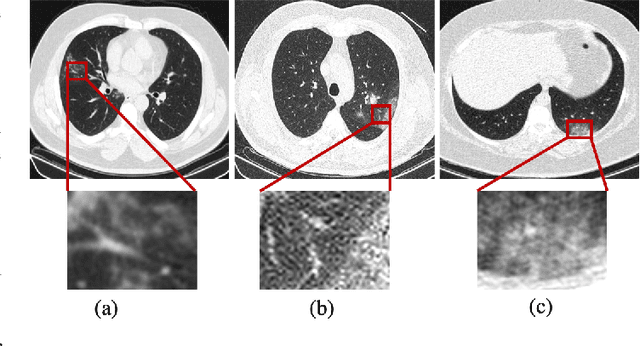

Abstract:The objective of this study is to develop a robust deep learning-based framework to distinguish COVID-19, Community-Acquired Pneumonia (CAP), and Normal cases based on chest CT scans acquired in different imaging centers using various protocols, and radiation doses. We showed that while our proposed model is trained on a relatively small dataset acquired from only one imaging center using a specific scanning protocol, the model performs well on heterogeneous test sets obtained by multiple scanners using different technical parameters. We also showed that the model can be updated via an unsupervised approach to cope with the data shift between the train and test sets and enhance the robustness of the model upon receiving a new external dataset from a different center. We adopted an ensemble architecture to aggregate the predictions from multiple versions of the model. For initial training and development purposes, an in-house dataset of 171 COVID-19, 60 CAP, and 76 Normal cases was used, which contained volumetric CT scans acquired from one imaging center using a constant standard radiation dose scanning protocol. To evaluate the model, we collected four different test sets retrospectively to investigate the effects of the shifts in the data characteristics on the model's performance. Among the test cases, there were CT scans with similar characteristics as the train set as well as noisy low-dose and ultra-low dose CT scans. In addition, some test CT scans were obtained from patients with a history of cardiovascular diseases or surgeries. The entire test dataset used in this study contained 51 COVID-19, 28 CAP, and 51 Normal cases. Experimental results indicate that our proposed framework performs well on all test sets achieving total accuracy of 96.15% (95%CI: [91.25-98.74]), COVID-19 sensitivity of 96.08% (95%CI: [86.54-99.5]), CAP sensitivity of 92.86% (95%CI: [76.50-99.19]).

Abstract:Reverse transcription-polymerase chain reaction (RT-PCR) is currently the gold standard in COVID-19 diagnosis. It can, however, take days to provide the diagnosis, and false negative rate is relatively high. Imaging, in particular chest computed tomography (CT), can assist with diagnosis and assessment of this disease. Nevertheless, it is shown that standard dose CT scan gives significant radiation burden to patients, especially those in need of multiple scans. In this study, we consider low-dose and ultra-low-dose (LDCT and ULDCT) scan protocols that reduce the radiation exposure close to that of a single X-Ray, while maintaining an acceptable resolution for diagnosis purposes. Since thoracic radiology expertise may not be widely available during the pandemic, we develop an Artificial Intelligence (AI)-based framework using a collected dataset of LDCT/ULDCT scans, to study the hypothesis that the AI model can provide human-level performance. The AI model uses a two stage capsule network architecture and can rapidly classify COVID-19, community acquired pneumonia (CAP), and normal cases, using LDCT/ULDCT scans. The AI model achieves COVID-19 sensitivity of 89.5% +\- 0.11, CAP sensitivity of 95% +\- 0.11, normal cases sensitivity (specificity) of 85.7% +\- 0.16, and accuracy of 90% +\- 0.06. By incorporating clinical data (demographic and symptoms), the performance further improves to COVID-19 sensitivity of 94.3% +\- pm 0.05, CAP sensitivity of 96.7% +\- 0.07, normal cases sensitivity (specificity) of 91% +\- 0.09 , and accuracy of 94.1% +\- 0.03. The proposed AI model achieves human-level diagnosis based on the LDCT/ULDCT scans with reduced radiation exposure. We believe that the proposed AI model has the potential to assist the radiologists to accurately and promptly diagnose COVID-19 infection and help control the transmission chain during the pandemic.